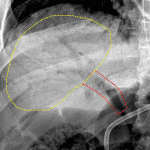

- NG tube is positioned with tip projecting at the GE junction

- Feeding tube tip overlies the proximal jejunum

- Diffuse distension of the stomach, small bowel, and colon with bubbly lucencies associated with bowel loops in the right and left lateral abdomen

- Portal venous gas

- Portal venous gas

- Pneumatosis

NG tube is positioned with tip projecting at the GE junction. Recommend advancing this tube 5-10 cm for placement within the stomach.

Portal venous gas with likely pneumatosis involving loops of bowel in the lateral right and left abdomen. These findings are concerning for bowel ischemia. Recommend surgical consultation and correlation with lactate values.